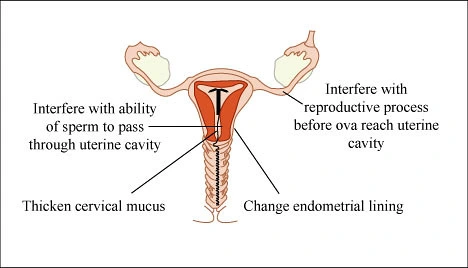

Emergency contraception pills function primarily by delaying or preventing the process of ovulation, which is the release of an egg from the ovary. If an egg is not released, there is no possibility of pregnancy. In addition, these pills may modify the cervical mucus to prevent sperm access to the uterus or alter the uterine lining, preventing a fertilized egg from implantation.

Most importantly, it is crucial to know that emergency contraception pills do not end a pregnancy. They do not function as abortion pills and therefore are ineffective should a woman already has an existing pregnancy.